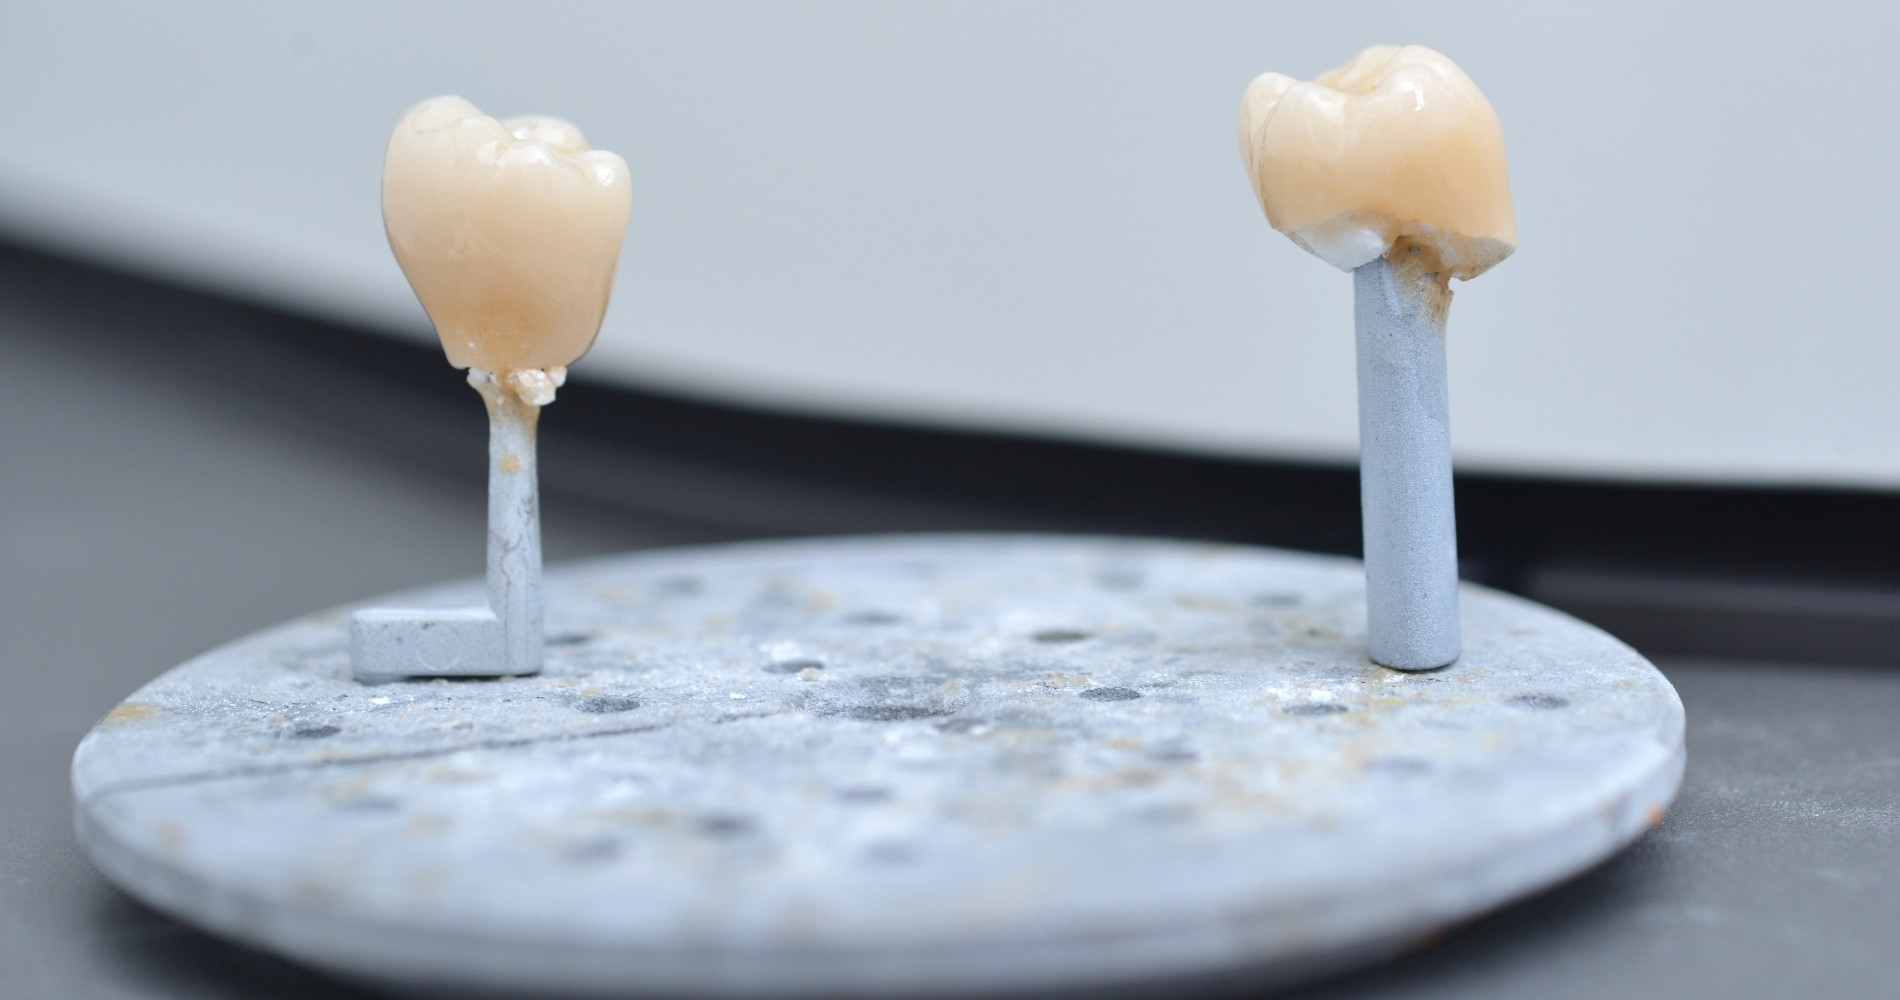

Pour chaque prothèse, nous sélectionnons des matériaux de haute qualité. En effet, nous evaluons leur résistance mécanique, leur biocompatibilité et leur rendu esthétique. Autant d’éléments qui assurent un résultat fiable et naturel.

Grâce à notre équipement de pointe, comme le scanner intra-oral et la conception assistée par ordinateur (CFAO), nous obtenons un ajustement très précis. De plus, ces technologies rendent le processus plus confortable et réduisent les retouches.

Selon les situations, nous utilisons la technologie CEREC. Cette technologie de pointe permet de fabriquer et poser certaines couronnes directement au cabinet en une seule séance. C’est un procédé qui évite les couronnes provisoires et réduit considérablement les délais.

COURONNES DENTAIRES

Les couronnes permettent de recouvrir et renforcer une dent fragilisée (carie profonde, fracture, traitement de racine). Nous les fabriquons sur place grâce à la technologie CEREC si possible pour un rendu naturel et durable.